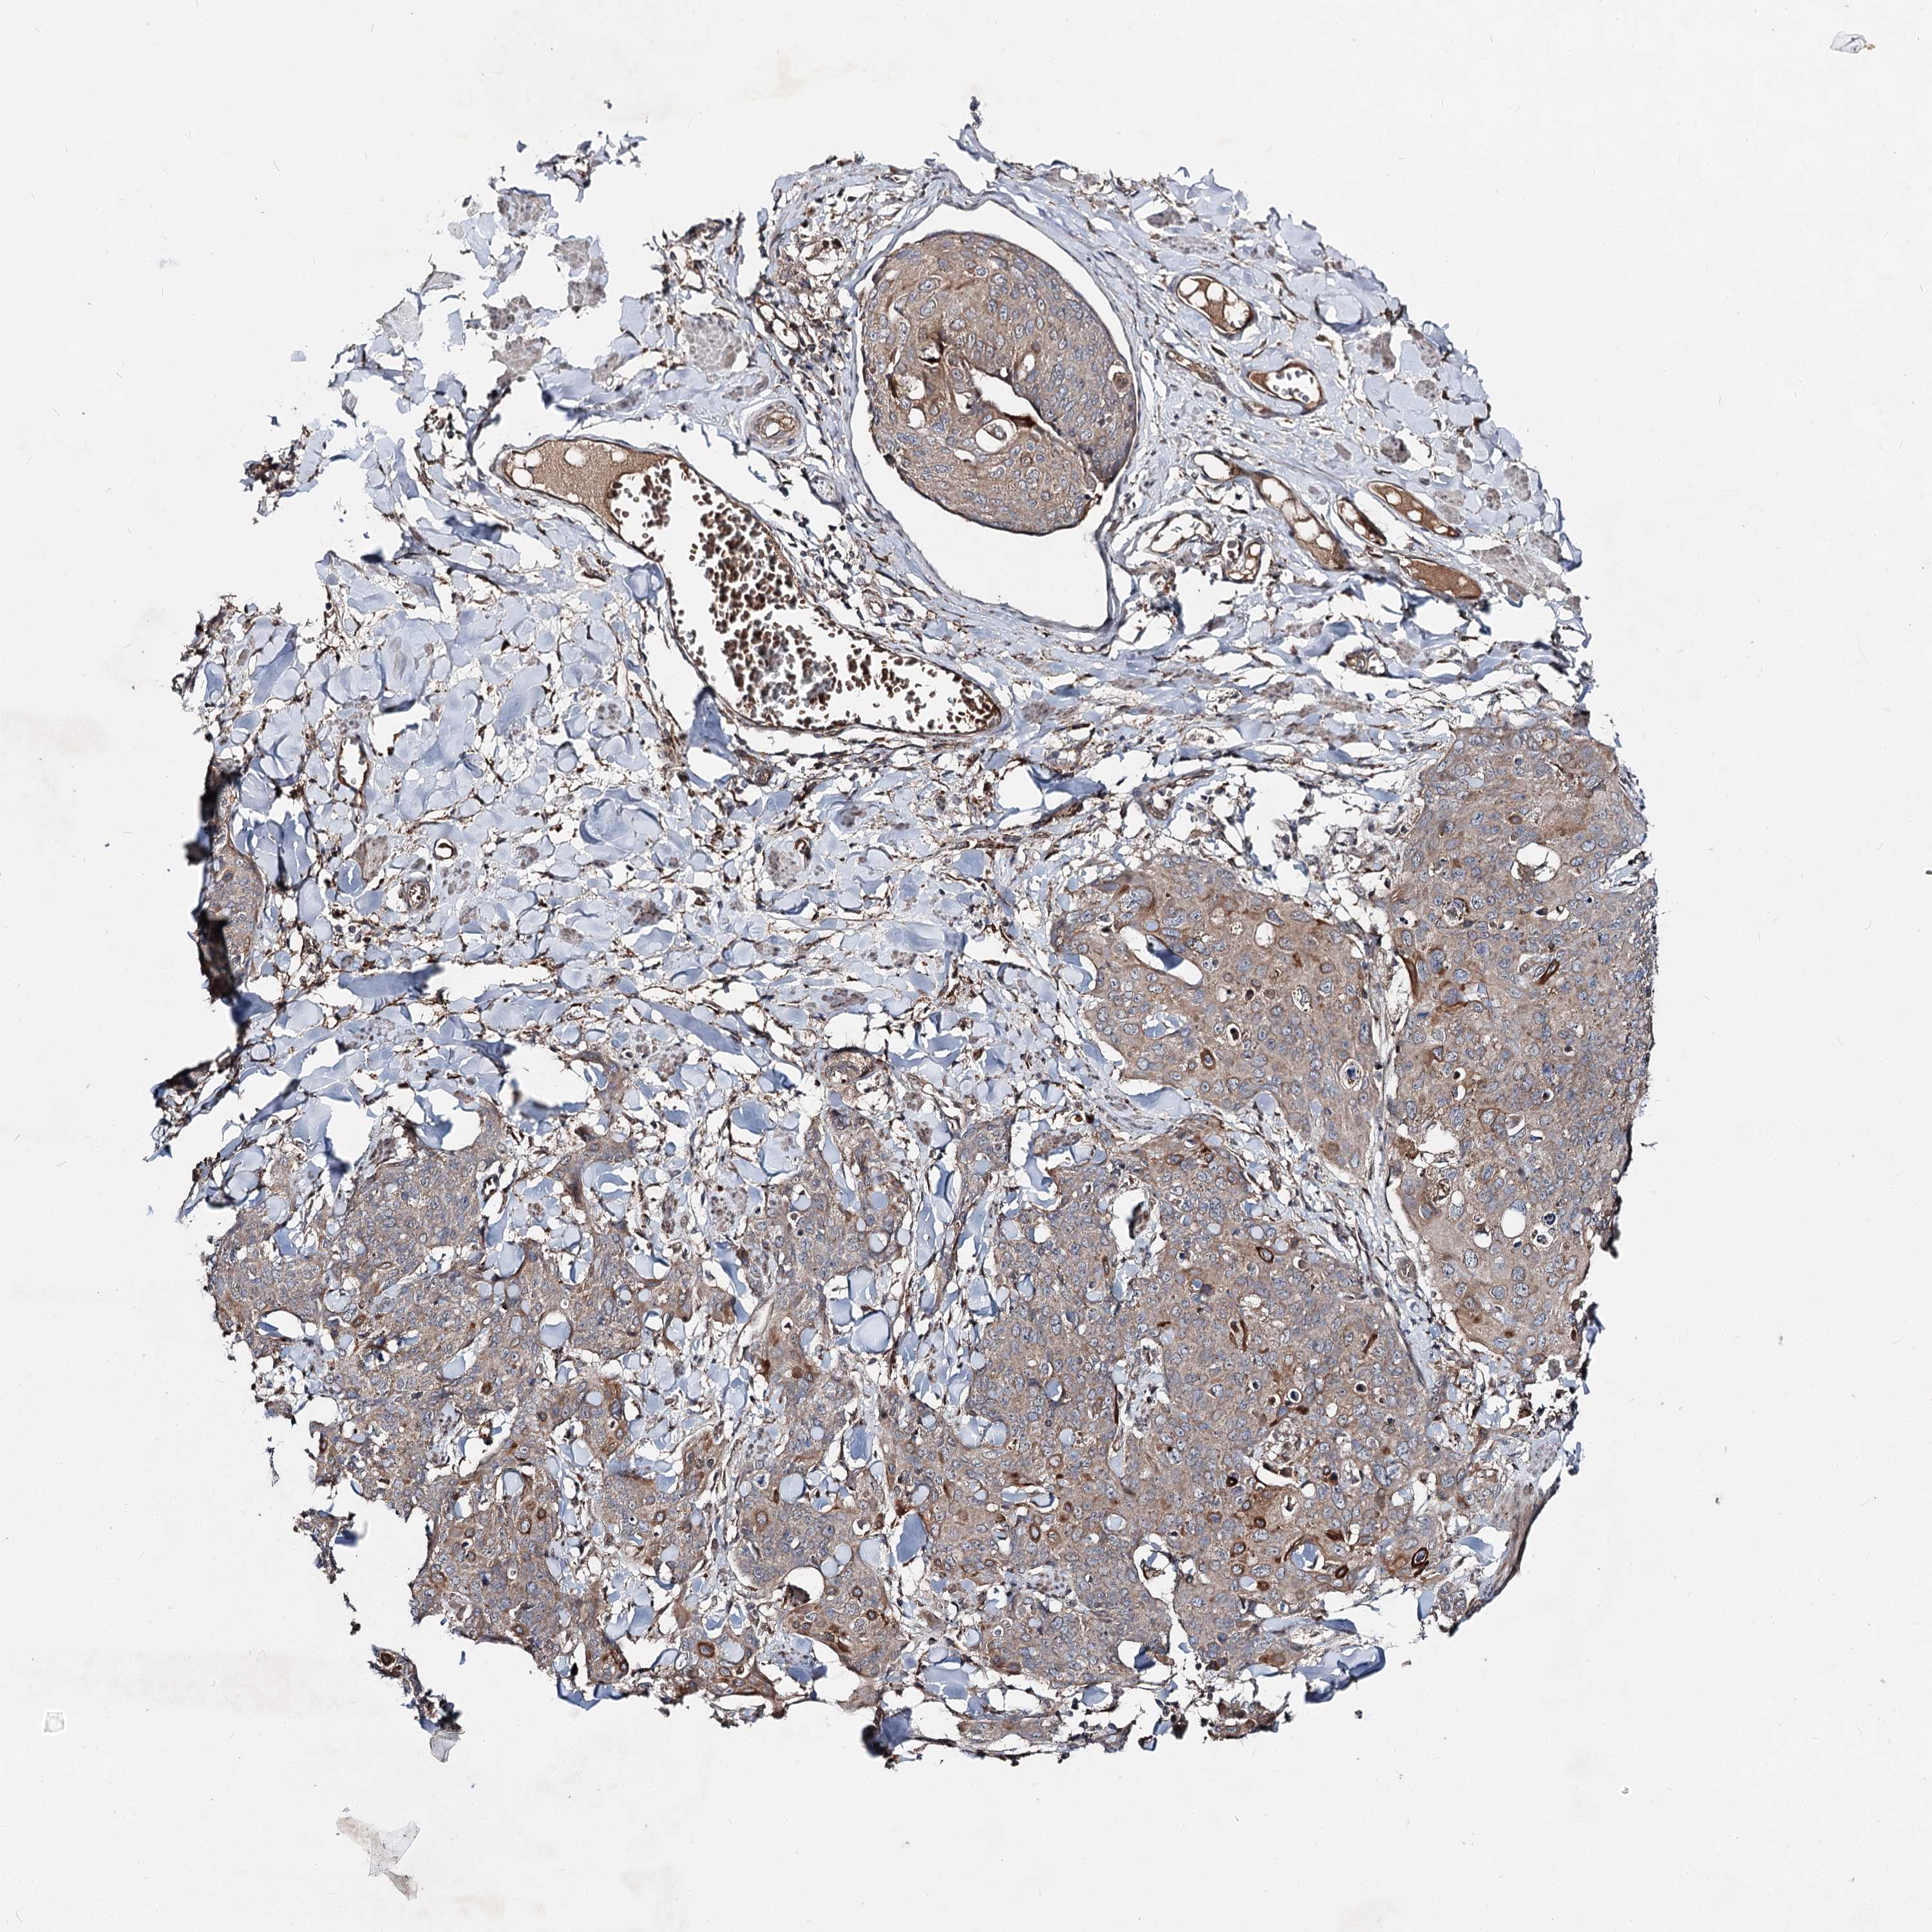

Basal cell and squamous cell cancer

SKIN CANCER - Protein expressioni

A mouse-over function shows sample information and annotation data. Click on an image to view it in a full screen mode. Samples can be filtered based on level of antibody staining by selecting one or several of the following categories: high, medium, low and not detected. The assay and annotation is described here.

Antibody stainingi

Antibody staining in the annotated cell types in the current human tissue is reported as not detected, low, medium, or high, based on conventional immunohistochemistry profiling in selected tissues. This score is based on the combination of the staining intensity and fraction of stained cells.

Each image is clickable and will lead to virtual microscopy that enables deeper exploration of all samples and also displays staining intensity scores, fraction scores and subcellular localization as well as patient and tissue information for each sample.

Antibody HPA038694

Antibody HPA038695

Staining

High

Medium

Low

Not detected

Intensity

Strong

Moderate

Weak

Negative

Quantity

>75%

75%-25%

<25%

None

Location

Nuclear

Cytoplasmic/membranous

Cytoplasmic/membranous,nuclear

Squamous cell carcinoma, metastatic, NOS